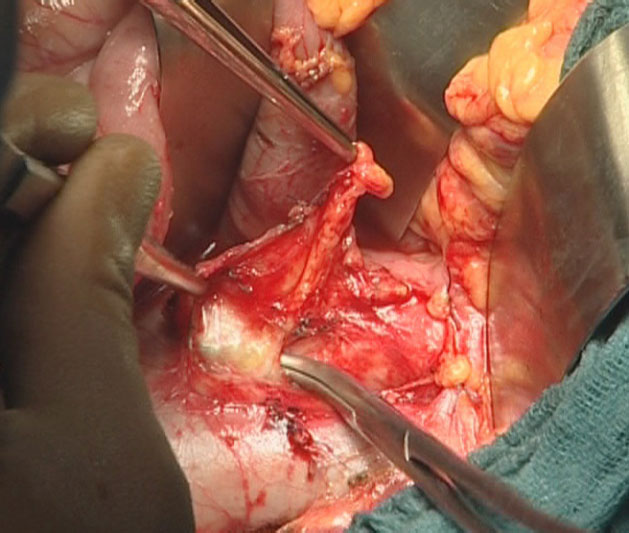

After dissecting the greater omentum from the transverse colon, the lesser sac and the entire anterior surface of the pancreas is exposed. A generous Kocher maneuver with mobilization of the ligament of Treitz (Figure 1) provides full mobilization of the duodenum and the pancreatic head.

The origin of the superior mesenteric artery just above the left renal vein is identified, dissected, and taped (Figure 2). The location and extent of the pancreatic head tumor is then evaluated, as well as the mobility of the head of the pancreas relative to the celiac axis and the superior mesenteric vessels. The vena cava and the left renal vein are identified. Lymph node sampling in the inter-aortico-caval area below the left renal vein is performed (Figure 3).

Next, the dissection of the plane between the pancreatic isthmus and the spleno-mesenterico-portal axis is performed to identify venous involvement. The decision to proceed with a mesenterico-portal vein resection is made at this juncture of the operation.